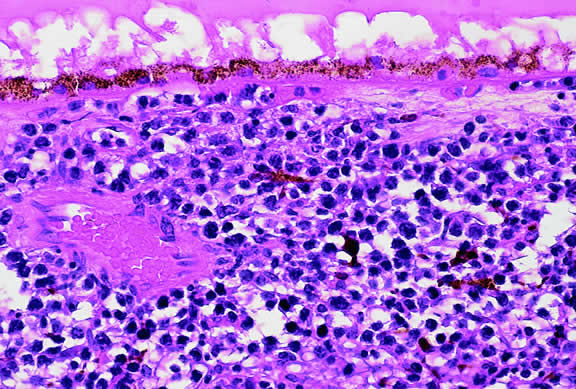

Although non-Hodgkin's lymphoma often affects the orbit and conjunctiva, intraocular involvement by lymphoma is relatively rare and occurs in two basic ways. First, patients who have widely disseminated systemic lymphoma may develop secondary ocular involvement whose typical manifestation is uveal infiltration. Second, in the variant of central nervous system (CNS) lymphoma that has been called primary lymphoma of the CNS and retina, the vitreous characteristically is involved and the uvea is spared. The latter entity also has been called vitreous large cell lymphoma or ocular “reticulum cell sarcoma.”205–208 In addition to the vitreous, the lymphoma cells also infiltrate the retina, and typically collect between Bruch's membrane and the retinal pigment epithelium, forming solid yellowish RPE detachments, which are highly suggestive of the diagnosis. This rare variant of primary CNS lymphoma should be suspected in older patients who have chronic vitritis that is unresponsive to therapy. Cytologic examination of diagnostic vitrectomy specimens reveals a highly cellular and extensively necrotic infiltrate that contains atypical lymphocytes with prominent nucleoli and protrusions of the nuclear membrane (Fig. 53). The significance of elevated vitreous interleukin 10 levels as a diagnostic marker for lymphoma is controversial.209,210

Fig. 53. Primary central nervous system lymphoma, vitreous. Diagnostic vitrectomy specimen contains large atypical lymphocytes, necrotic lymphoid cells, and nuclear debris. Lymphoma cells in inset have nuclear membrane protrusions and prominent nucleoli. Main figure, Millipore filter. (Hematoxylin-eosin, × 250.)